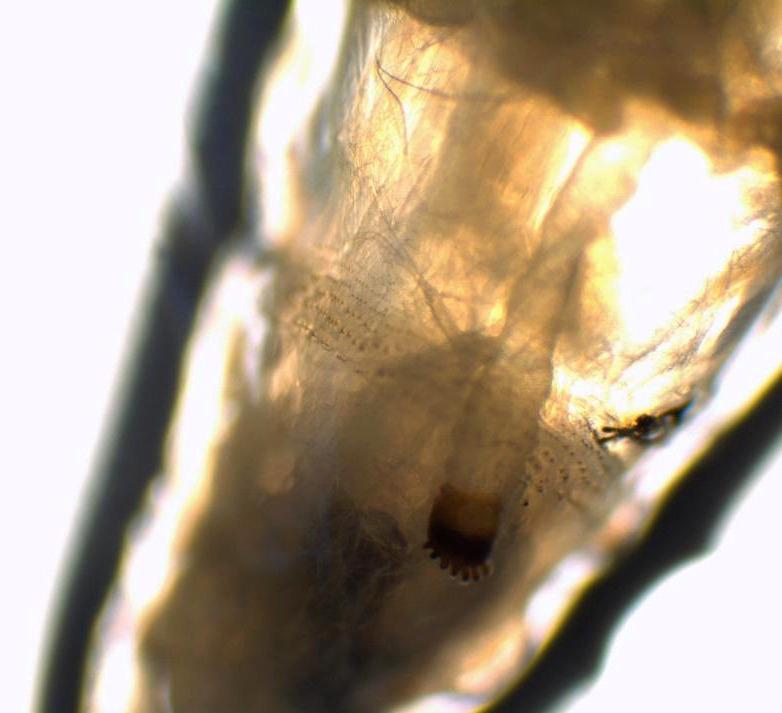

Myiasis is the infestation of living bodies of animals and humans with fly larvae or maggots. These accidental or obligatory parasites grow in three stages in the host while feeding on his tissues. Myiasis in a hospital area is a rare situation when flies accidentally lay their eggs on patients, mostly in open wounds or cavities. Case presentation. We report a case of a 72-year-old patient admitted to a general surgery department for peritonitis, then to an intensive care unit (ICU) for septic shock where he was intubated. Some maggots were seen moving in his nasal cavity a few days after his admission and were sent to our laboratory for examination. The larvae were identified as the third larval stage of sp. They were removed entirely after intense nasal washing. A checking examination of his nasal cavities revealed no evidence of further infestation. After nasal washing, no other larvae were seen but unfortunately, the patient died of septic shock a few days later.

Few cases of nasal myiasis in hospitalized patients were reported. ICU myiasis, extremely rare, is caused by the patient's inability to fend off the flies because of their conscious state, presence of blood or odors caused by infections, and the warm humid environment.